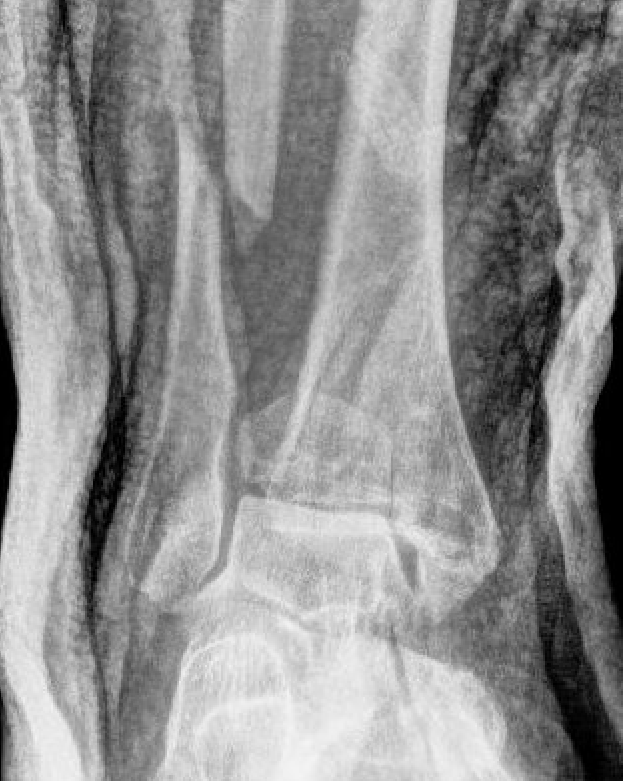

Dislocated ankle joint with large posterior malleolus

Articular incongruency

Posterior malleolus and syndesmotic injury